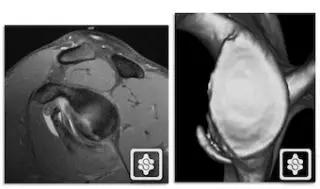

3. 骨性 Bankart 损伤(Bony Bankart lesion)

下盂肱韧带盂唇复合体损伤同时伴有关节盂前下方的撕脱性骨折。由于关节盂前下方的骨质缺损,可以导致梨形的肩盂变为「倒梨形」结构,出现关节不稳的主要因素。

骨性 Bankart 损伤的 MR(左)和 CT(右)(来源:ShoulderDoc)

骨性 Bankart 损伤的 MR(左)和关节镜图(右)(来源:ShoulderDoc)